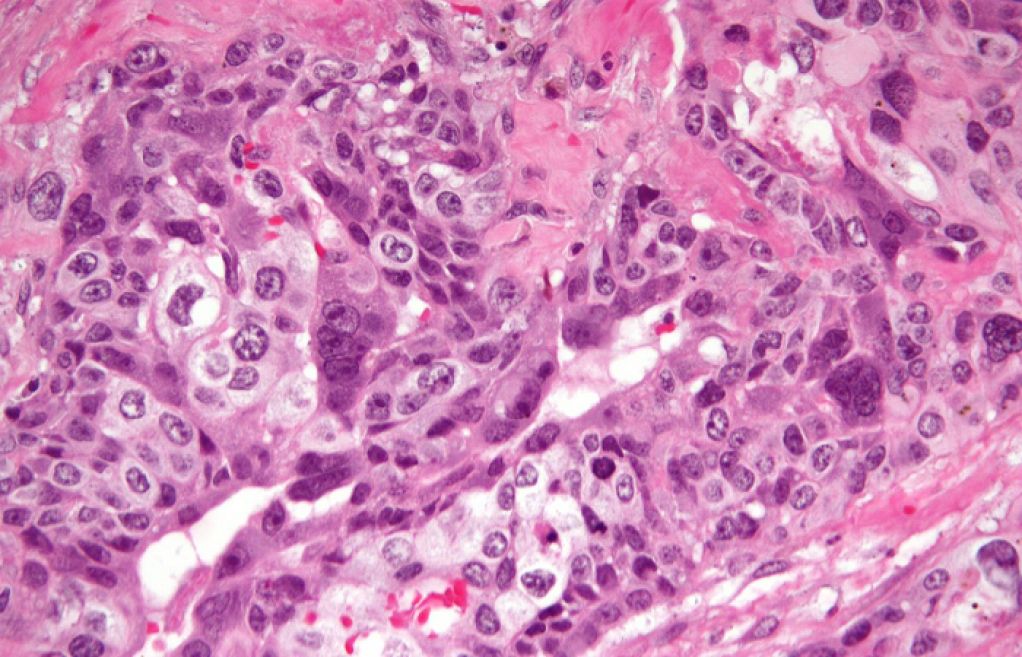

پاکستانی شوبز انڈسٹری کی سابق اداکارہ اریج فاطمہ نے اپنی زندگی کے انتہائی مشکل دور کا انکشاف کر کے مداحوں کو حیران کر دیا ہے۔ انہوں نے بتایا کہ انہیں ایک نایاب اور بہت تیزی سے پھیلنے والا کینسر، کوریوکارسینوما، کی تشخیص ہوئی ہے، جو عام طور پر مولر حمل کے بعد ظاہر ہوتا ہے۔

انہیں کوریوکارسینوما نامی کینسر کی تشخیص ہوئی ہے۔

کوریوکارسینوما ایک نایاب اور بہت تیزی سے پھیلنے والا کینسر ہے جو حمل کے دوران یا حمل کے بعد رحم میں پیدا ہو سکتا ہے، خاص طور پر مولر حمل کے بعد۔